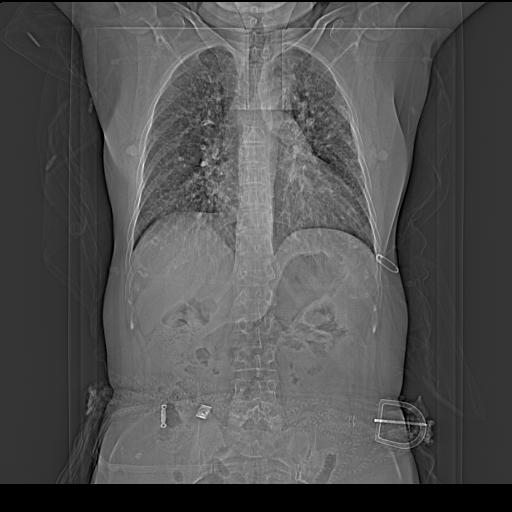

老年女性,嗜睡3天,意识模糊。轻咳,无发热。

双肺多发淡片影,毛玻璃影,,支持支气管肺炎,,建议血气找原因,,嗜睡是否肺性脑病?有没有慢支病史?

双肺炎症,建议抗炎治疗后复查,见过几个老年肺炎病例,没有发烧、咳嗽症状,直接以昏迷就诊。

1)两肺感染性病变;建议抗炎治疗后复查。2)纵隔淋巴结肿大。3)左侧胸腔积液。

1)先考虑两肺感染性病变;建议抗炎治疗后复查。

2)纵隔淋巴结肿大。

3)左侧胸腔积液。